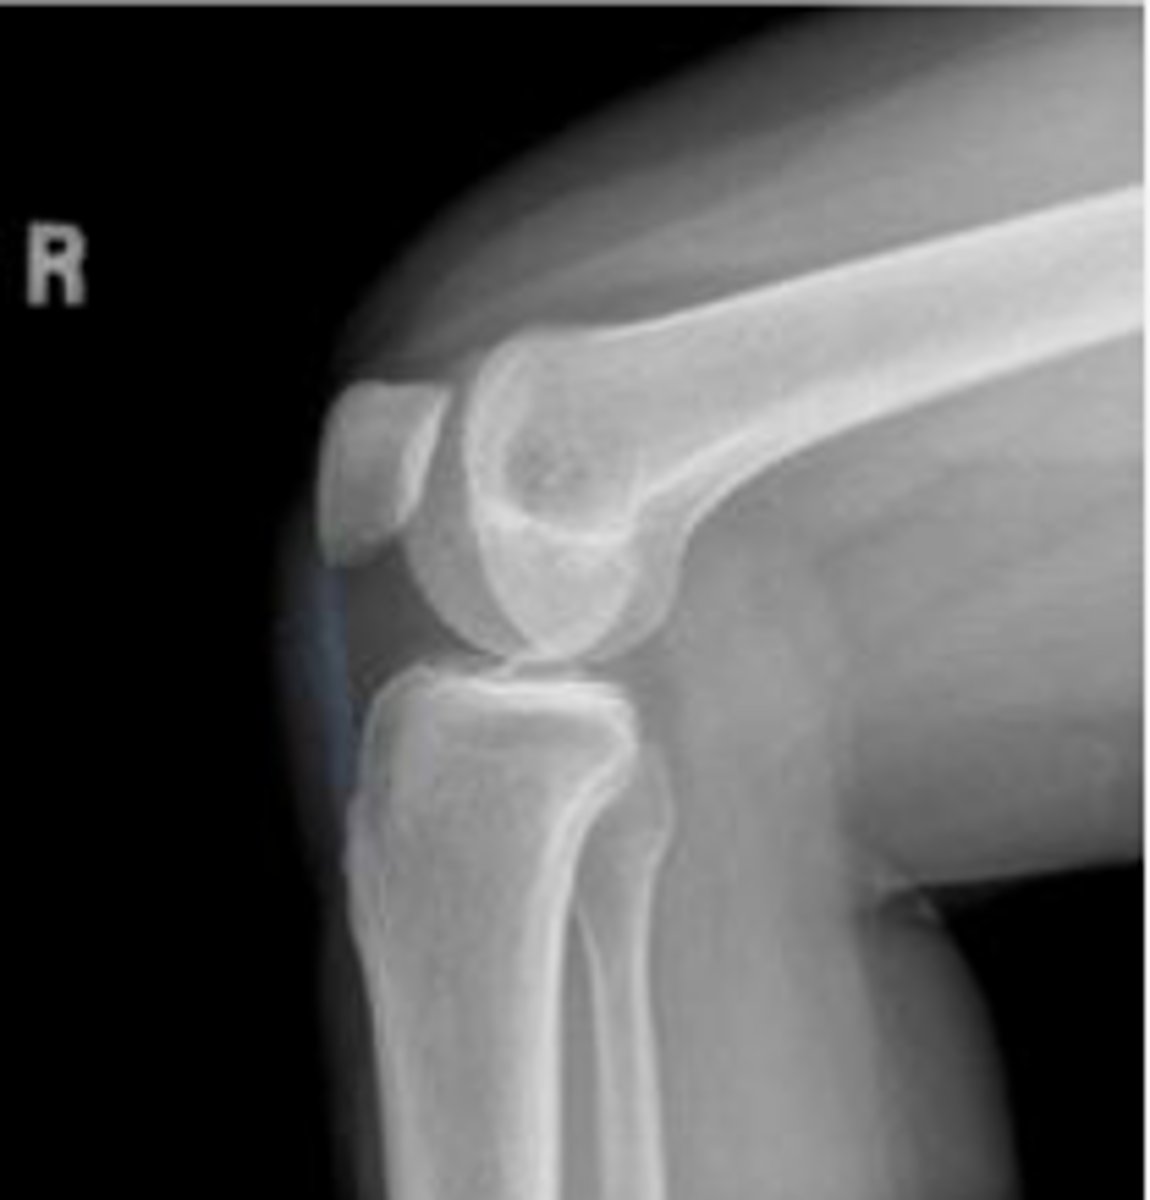

Right lateral knee

What is the name of the radiographic view?

Lateral tibiofemoral alignment of the left knee

What is the assessment?